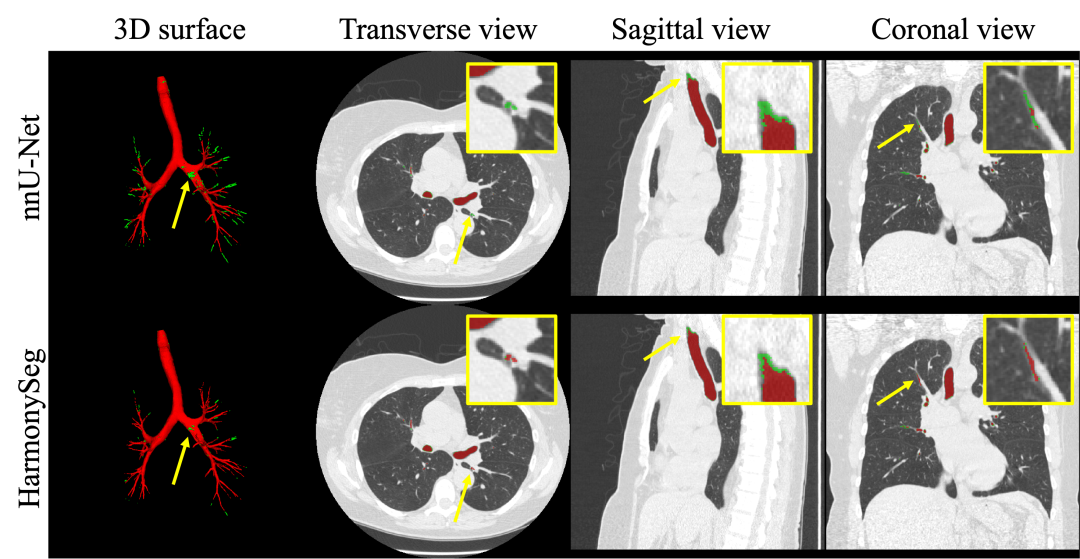

图4. 肝脏血管分割结果示例。红色表示分割结果,绿色表示对应标签。黄色箭头突出改进之处。

图6. 气管树分割结果示例。

在HVS任务中,HarmonySeg在衡量分割整体性能的Dice和血管树连通性的clDice上都实现了最优的性能,F1-score的优化也表明HarmonySeg在recall和precision之间实现了有效的平衡。其他任务中HarmonySeg也表现良好。整体来看,HarmonySeg在上述任务中均表现出了具有竞争力的性能,在多项指标上领先于已有模型。